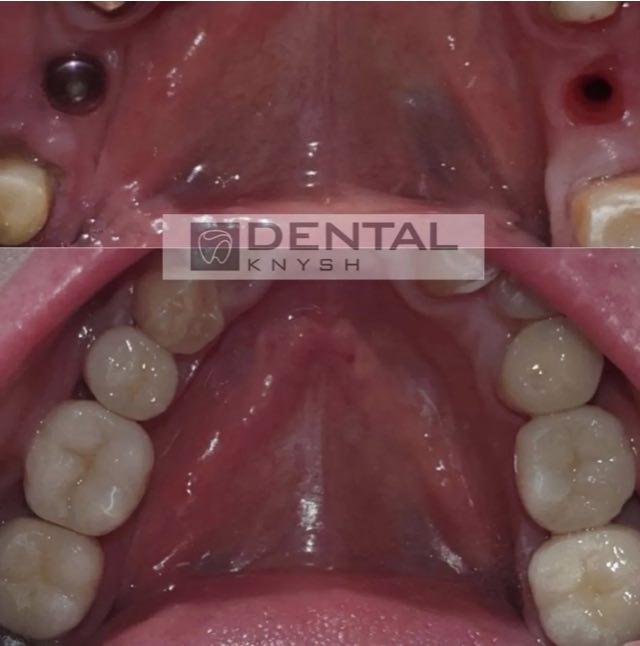

Фото отчет: имплантация зубов, две челюсти 2026-06-11

Имплантация зубов верхней челюсти, 2026-04-14, фото до/после

Имплантация зубов верхней челюсти, 2026-04-15, фото до/после

Фото-отчет: имплантация верхней челюсти, 2026-04-12

Фото-отчет: имплантация и керамические виниры, 2026-04-12

Фото-отчет: имплантация верхней челюсти, 2026-04-13

Имплантация зубов верхней челюсти, фото к/после, 2026-04-17

Имплантация зубов верхней челюсти, 2026-04-17

Фото отчет: all-on-4 — имплантация обеих челюстей, 2026-03-10

Фото отчет: all-on-4 — имплантация обеих челюстей — 24 коронки, фото публикуются с разрешения пациента, 2026-01-21

Фото отчет: имплантация верхней челюсти, 2026-04-06

Фото отчет: имплантация верхней челюсти – 14 коронок на 6 имплантах, фото и КТ публикуются с разрешения пациента, 2026-01-12

Фото отчет: имплантация верхней челюсти, 2025-12-05

Фото отчет: имплантация зубов, коронки, фото публикуется с разрешения пациента, 2025-12-14

Фото отчет: полная имплантация зубов, каждая челюсть все на 4 имплантах (all-on-4), фото публикуется с разрешения пациента, 2025-07-20

Фото отчет: имплантация зубов обеих челюстей до/после, 2025-05-07 (фото публикуется с разрешения пациента).

Фото отчет: имплантация зубов обеих челюстей до/после, 2025-05-05 (фото публикуется с разрешения пациента).

Фото отчет: имплантация зубов обеих челюстей на 12 имплантах, 2025-04-19 (фото публикуется с разрешения пациента).

Фото отчет: имплантация зубов верхней челюсти на 6 имплантах (all-on-6) и имплантация отдельных зубов нижней челюсти, 2025-01-26 (фото публикуется с разрешения пациента).

Фото отчет: имплантация зубов обеих челюстей на 10 имплантах, 2024-12-25 (фото публикуется с разрешения пациента)

Фото отчет: имплантация обеих челюстей на 10 имплантах, 2024-10-07 (публикуется с разрешения пациентки)

Фото отчет: имплантация двух челюстей в DentalKnysh (2024-06-20) или как мгновенно помолодеть на 20 лет

Фото отчет: имплантация зубов, 24 коронки на имплантах и зубах, 2024-05-18

Фото отчет по имплантации верхней челюсти: было установлено 14 циркониевых коронок на 6 имплантах, 2024-04-24

Фото отчет: импланты, коронки, виниры в DentalKnysh, 2024-02-15

Фото отчет: импланты, коронки, виниры в DentalKnysh, 2024-02-15

Фото отчет пародонтологического лечения и имплантации полной верхней челюсти и частично нидней, удаление всех зубов на верхней челюсти и некоторых на нижней (были большие воспалительные процессы и кисты на верхушках корней зубов).

За одну операцию удалили все необходимые зубы и установили 10 имплантов и временный пластмассовый протез на имплантах, что позволило пациенту не ходить без зубов, пока импланты не приживутся.

Через 6 месяцев заменили временный протез и постоянную несъемную конструкцию из циркона и получилась такая хорошая улыбка.

Фото отчет по имплантации обеих челюстей было установлено 28 циркониевых коронок на 12 имплантах 2024-01-31

Фото отчет по имплантации верхней челюсти от 2024-01-04: было установлено 14 циркониевых коронок на 6 имплантах

Фото отчет: 6 имплантов, циркониевый протез 12 ед, 2023-08-22

Фото отчет 11 имплантов от 2023-04-30

Фото отчет от 2023-04-04 коронки на 6 имплантах на нижней и верхней челюсти:

Фото отчет от 2023-03-22: коронки на 6 имплантах на нижней челюсти и коронки на 4 имплантах на верхней челюсти:

Фото отчет от 2022-11-15, нижняя челюсть на 6 имплантах и коронки на верхней челюсти (5 фото)